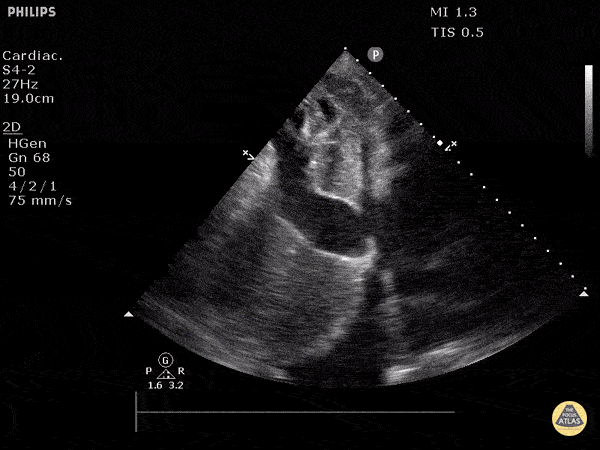

This is a subxiphoid long axis view of the IVC demonstrating significant enlargement with minimal collapse with respiratory variation. The hepatic vein is also seen entering the IVC and is noted to be quite distended consistent with very high filling pressures. Justin Bowra MBBS, FACEM, CCPU Emergency Physician, RNSH et al. (Dr. Vahtrick)